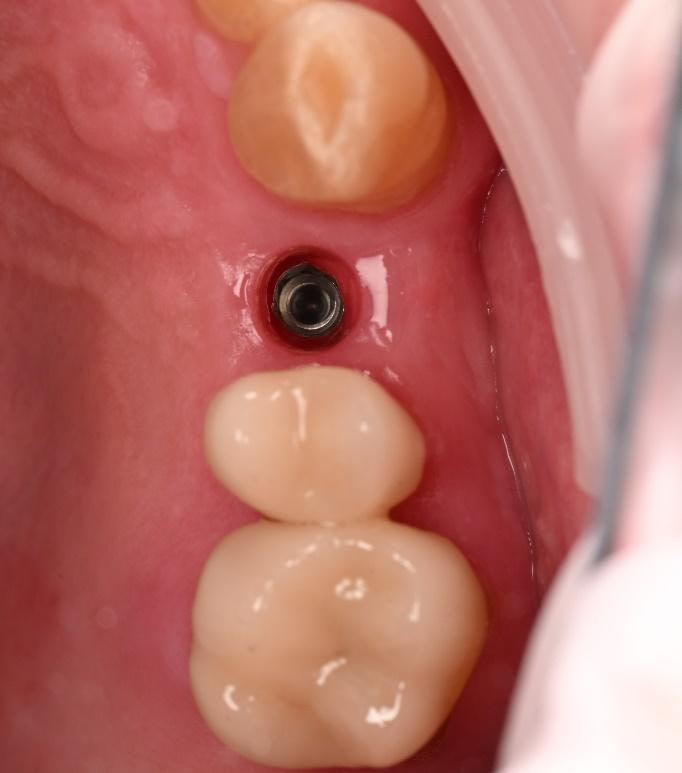

Three months after the implant surgery, a thorough post-operative assessment revealed excellent healing and implant stability.

Digital impressions were captured using the TRIOS 4 intraoral scanner, and the implant-supported crown was designed using 3Shape Design Studio.

Implant detection matches the scan body in the intraoral scan with the digital library. A colour scale is given to show the accuracy of the matching (Green is good).